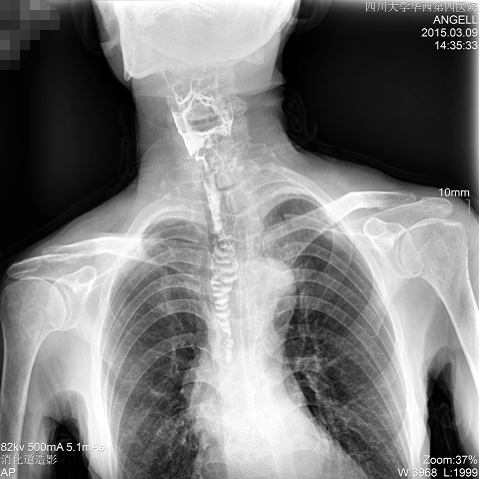

如下圖所示:該患者因吞咽時感到很難受,進食時也經(jīng)常咳嗽故就醫(yī)診斷。使用多功能dr為病人進行消化道造影診斷,要求他吞鋇后發(fā)現(xiàn),食道各段通過順利,形態(tài)規(guī)則,雙側(cè)梨狀窩不對稱左側(cè)稍淺,多次吞咽動作后,仍見鋇劑滯留,并見鋇劑進入氣管,屬于會厭征陽性。會厭功能紊亂,鋇劑進入了氣管。

圖為正位:通過動態(tài)影像可以清楚看到鋇劑進入了支氣管道且雙側(cè)梨狀窩不對稱

通過多功能dr可以診斷該病人的癥狀為會厭功能紊亂,鋇劑進入到了氣管。而在動態(tài)透視下可以清晰的觀察到鋇劑從何處進入氣管,可清晰顯示食管粘膜結(jié)構(gòu)。使用多功能dr其獨特的視頻采集技術(shù),可實時保存視頻并能實現(xiàn)900萬像素實時點片,才能獲取這樣清晰的病灶點。而常規(guī)dr只能拍攝靜態(tài)片,且成像效果大打折扣,因此較難確診病灶。